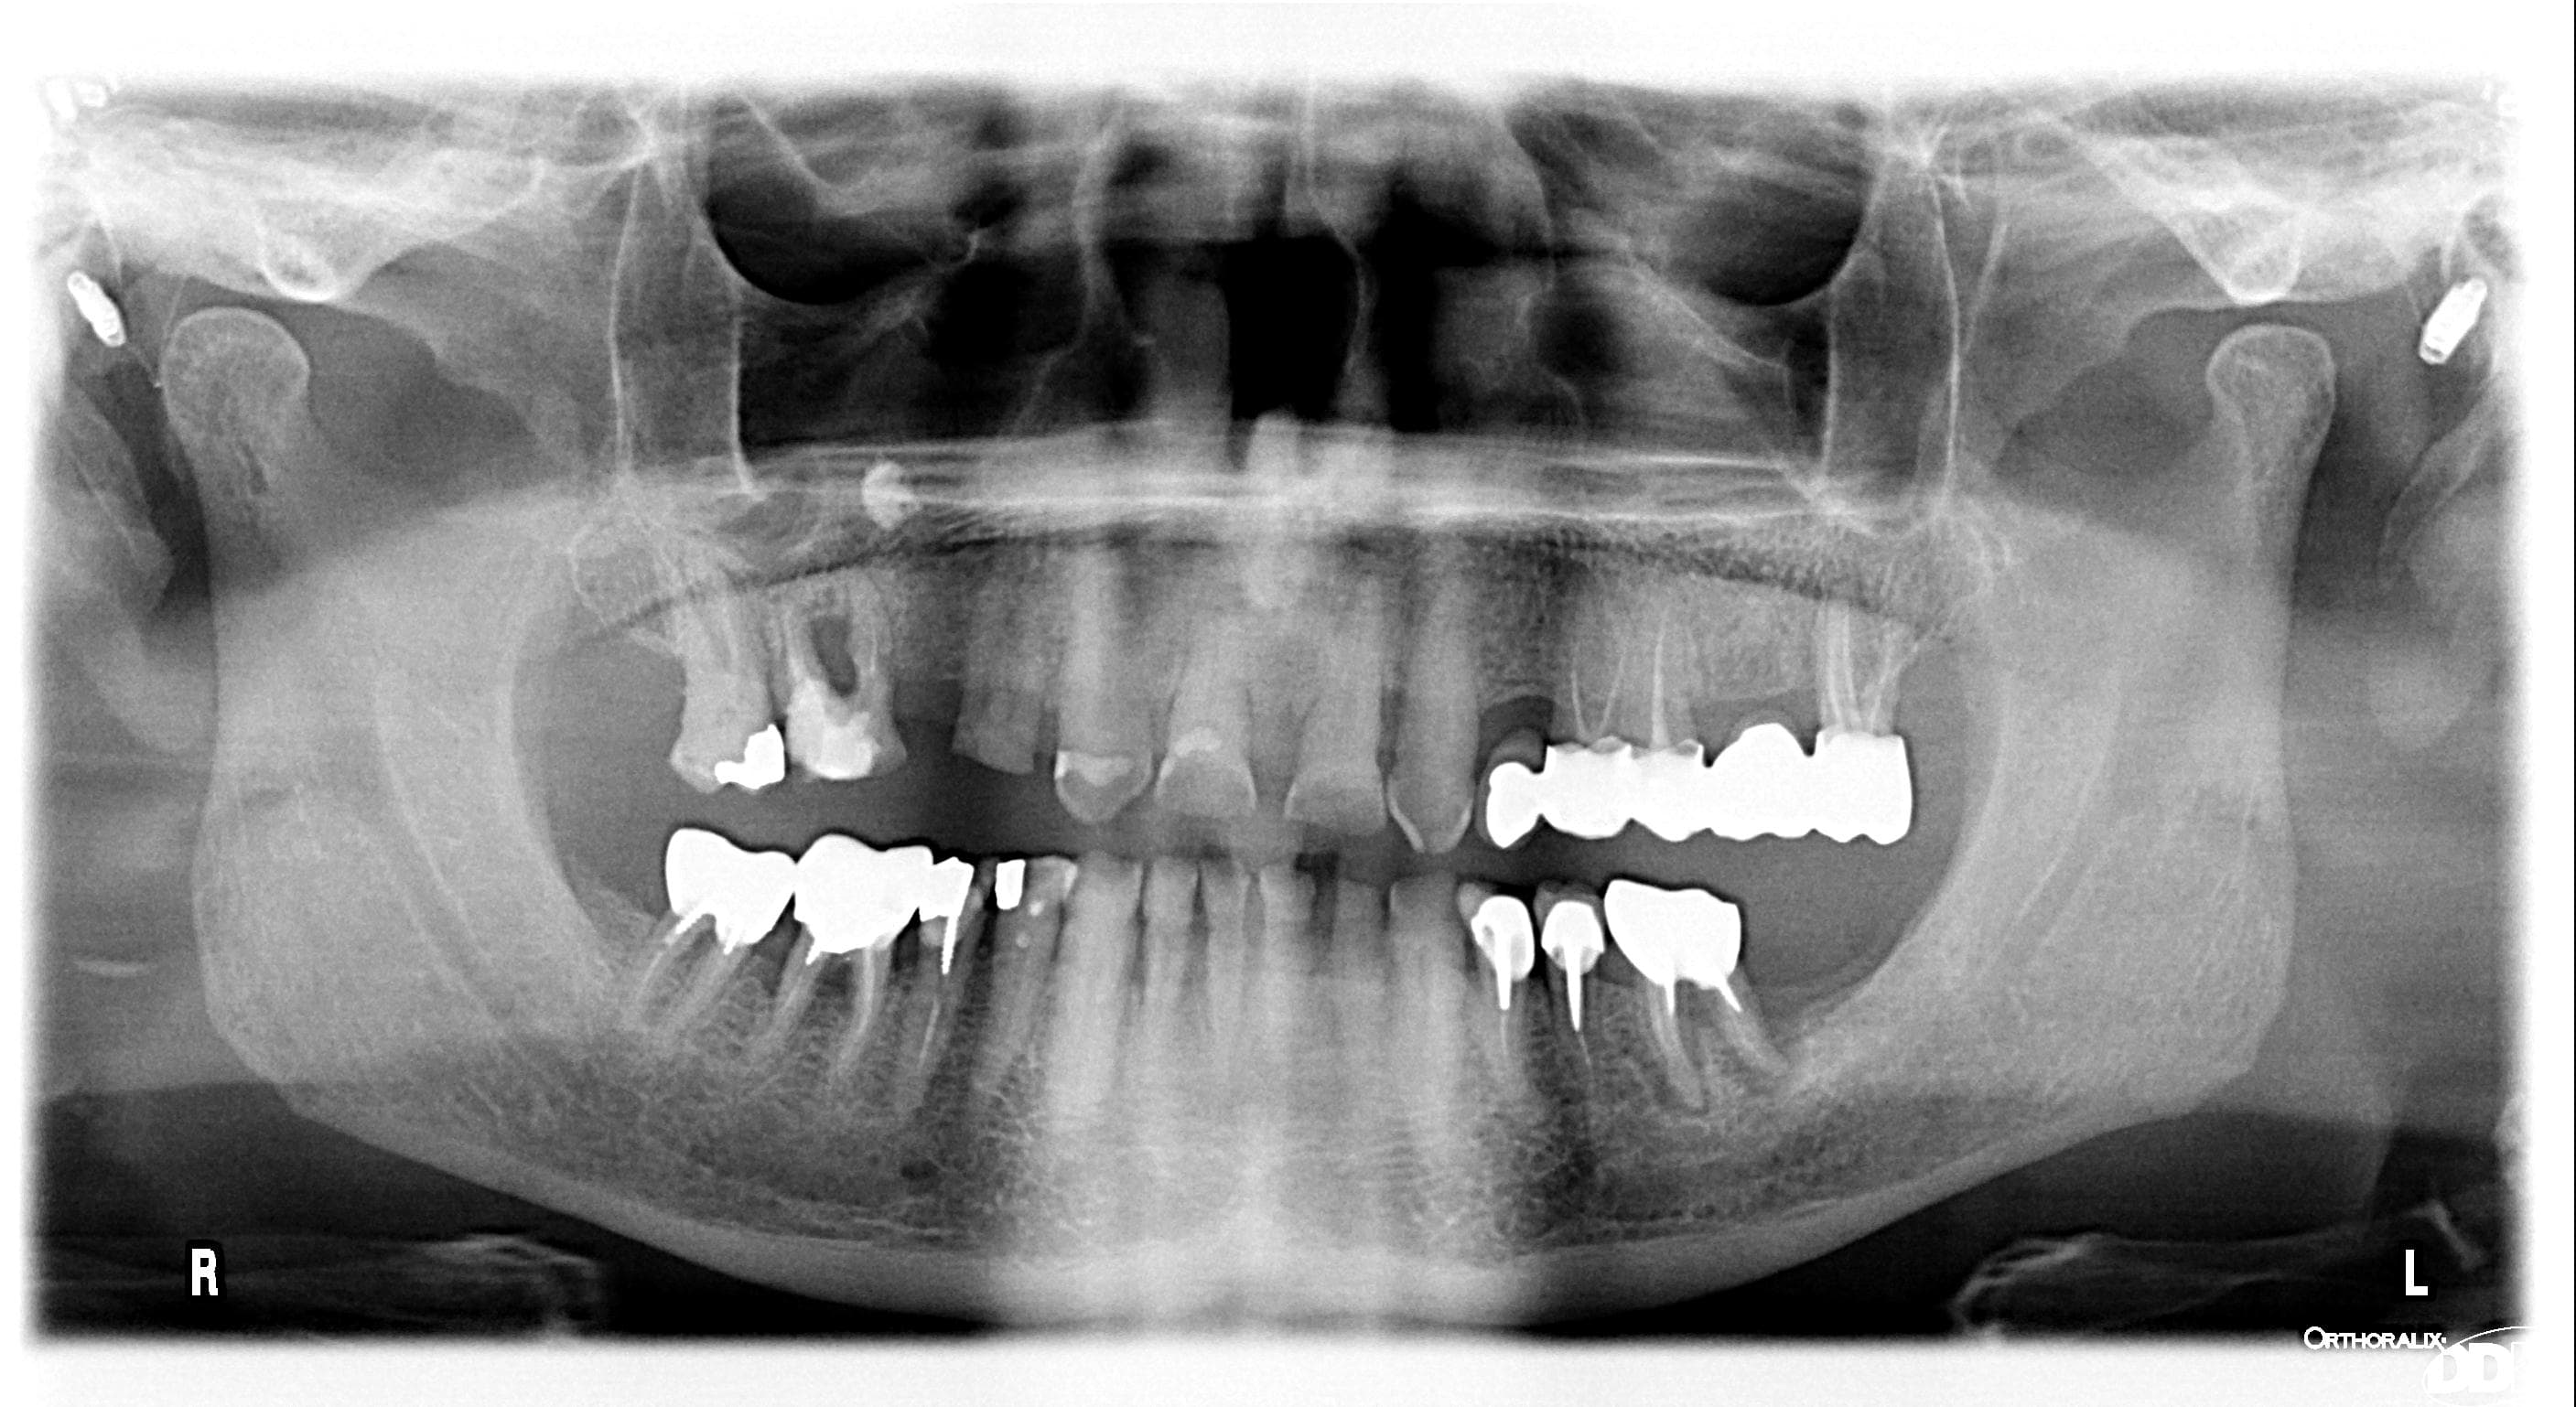

Patient sympa 75 ans sur j'ai fait en avril 23 un bridge 13-17, piliers 13, 14, 17 (dents vivantes parce que ... dents vivantes et ta gueule) inters 15, 16.

pas cool, la première réflexion qui me vient à l'esprit c'est que ton humour est meilleur que ton endo... par contre pas simple de donner une marche à suivre, peut être qu'un pano permettrait d'avoir une vue plus globale ...

Comme pxav a minima une pano pour un éventuel plan de traitement

ton pano, montre clairement que le problème de ton patient ne s’arrête pas à la 17...

Factuellement, on voit sur cette panoramique des pathologies multiples à traiter, qui ne sont vraisemblablement pas traitées car asymptomatiques, qu'il ait 75 ou 35 ans, et que le praticien ait 2 ans ou 40 ans d'expérience, ne change rien à cette réalité.